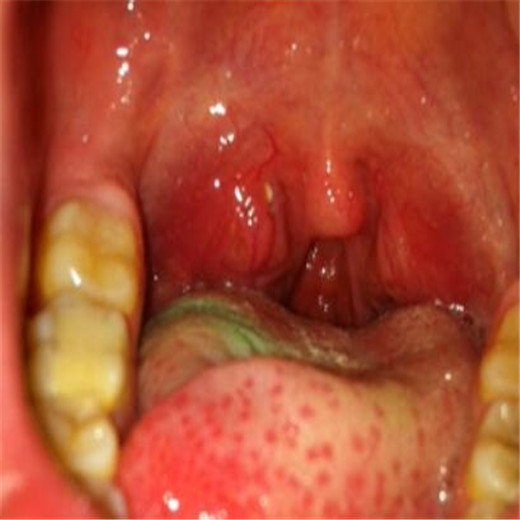

扁桃體炎圖片

扁桃體腫大